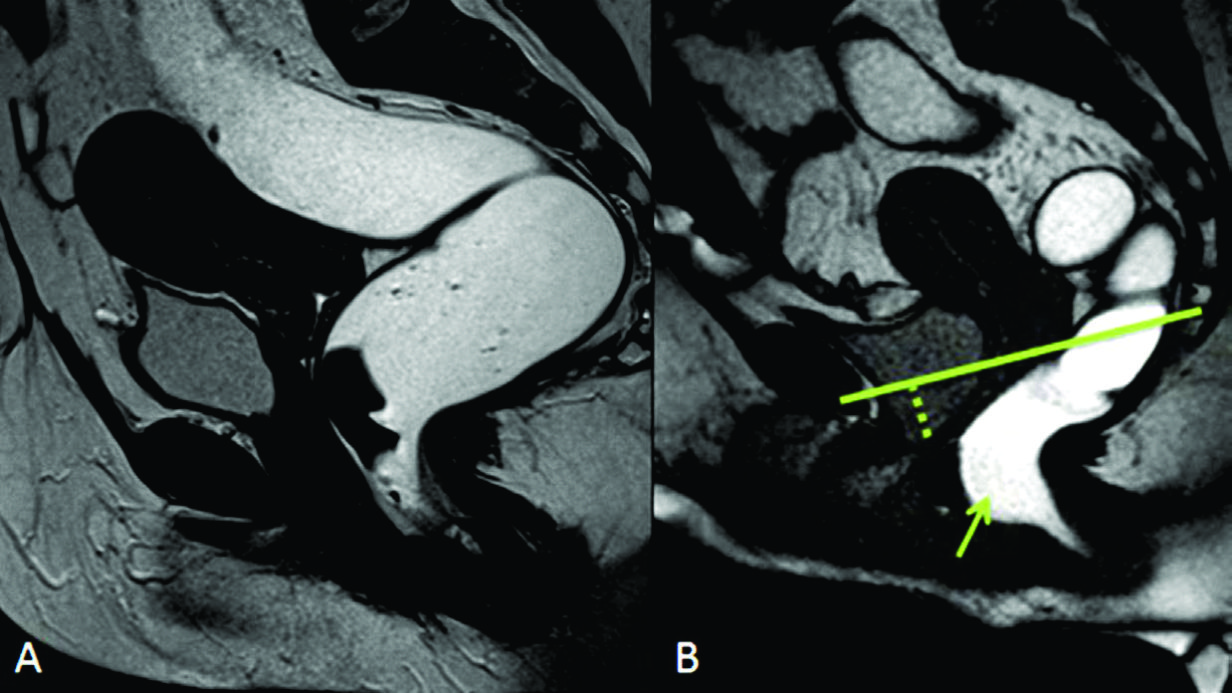

Figura 14

Cistocele y rectocele anterior

A) Imágenes potenciadas en T2 de alta resolución en el plano sagital. B) TRUE FISP sagital durante defecación. Se identifica cistocele y rectocele anterior tanto en el reposo como durante las maniobras dinámicas. Cistocele (punteado) y rectocele anterior (flecha).